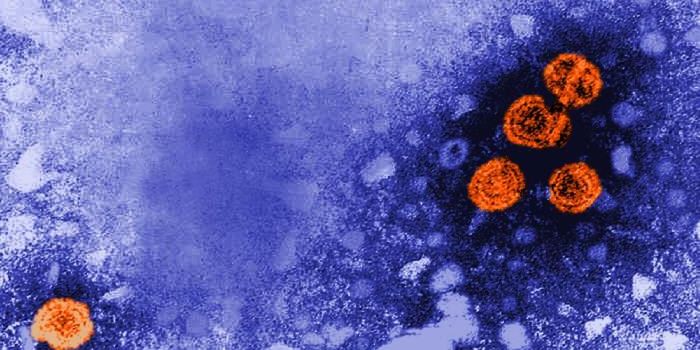

MAR 15, 2020MicrobiologyNew research has suggested that after long-term follow-up, HIV is no longer detectable in a patient that was previously ...

SEP 20, 2021Genetics & GenomicsHuman immunodeficiency virus (HIV) is a retrovirus, which is a type of virus that can write its genetic material into th ...